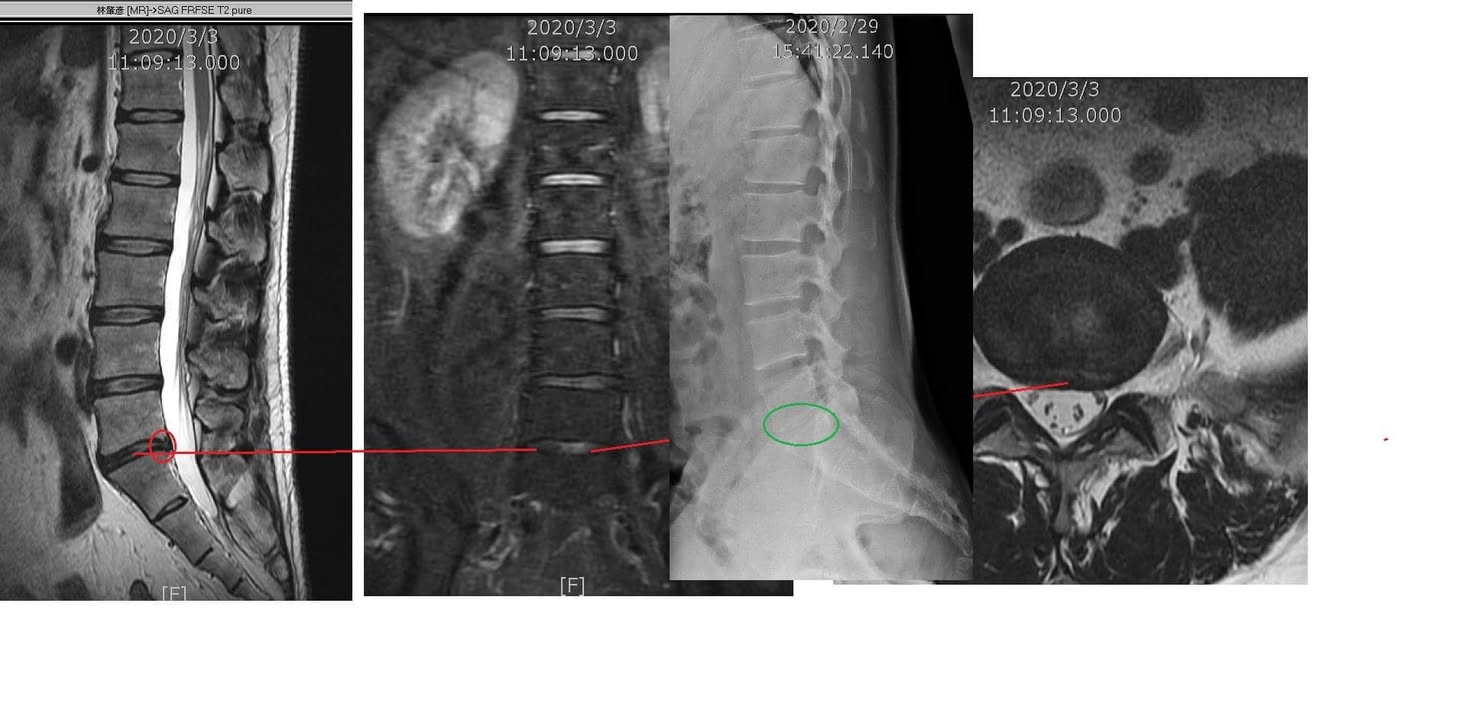

Cervical Spine Treatment Cases 腰椎治療案例 #今天來聊巨大骨刺為何可以吸收回去! #椎間盤突出需要多久才能吸收呢? #馬尾神經症候... 2020.09.08 #典型假性坐骨神經痛 #原來是梨狀肌症候群 #核磁共振排除椎間盤突出 #抽絲剝繭真相大... 2020.08.13 #嚴重椎管狹窄醫案 #感謝台北林大哥熱情見證 #從寸步難行到輕快漫步 #鍛鍊多裂肌的重... 2020.08.12 #椎間盤突出可以吸收回去嗎 #微針治療原理是什麼 #何時一定要接受神外開刀 #一張圖秒... 2020.08.11 #感謝花蓮鄉親林大姐熱情見證 #一分鐘認識椎管狹窄 #原本痛到無法走路打算開刀了 #脊... 2020.08.01 #感謝新莊區林先生熱情見證 #椎間盤突出跟纖維環裂隙的關係 #纖維環破裂突出可以不... 2020.07.28 #逆轉勝又一發case #原本疼痛一年多想說一定要手術治療了 #八週治療後症狀全部消失 #... 2020.07.25 #巨大椎間盤突出一定要開刀嗎 #除了開刀以外的選擇 #感謝台北市吳先生熱情見證 2020.07.24 #腰椎滑脫的疼痛心酸誰人知啊 #一分鐘瞭解腰椎滑脫 #哪一種情況需要積極開刀 #要如何... 2020.07.21 #巨大椎間盤脫垂一定要開刀嗎? #感謝新店林先生熱情見證受訪 #西醫手術有那些選擇... 2020.07.02 #纖維環裂隙AnnularFssures #MRI看起來不嚴重卻嚴重困擾患者 #感謝桃園市蕭先生熱情見... 2020.06.19 #骨刺有可能吸收回去嗎?? #疼痛超過六年的特殊案例探討 #MRI核磁共振前後對比 #感謝... 2020.06.14 #坐骨神經痛一定要開刀嗎 #突出的骨刺真的可以自己吸收嗎 #最新英國醫學期刊BMJ的看... 2020.05.30 #骨刺跟突出髓核有可能吸收回去嗎?? #特殊案例探討 #核磁共振一年後對比 2020.05.29 #從醫以來第一次碰到薦椎Tarlov cyst囊腫#左邊紅色圈圈是個案,右邊是國外案例#腰... 2020.05.23 ← 上一頁 10 11 12 13 14 下一頁 →